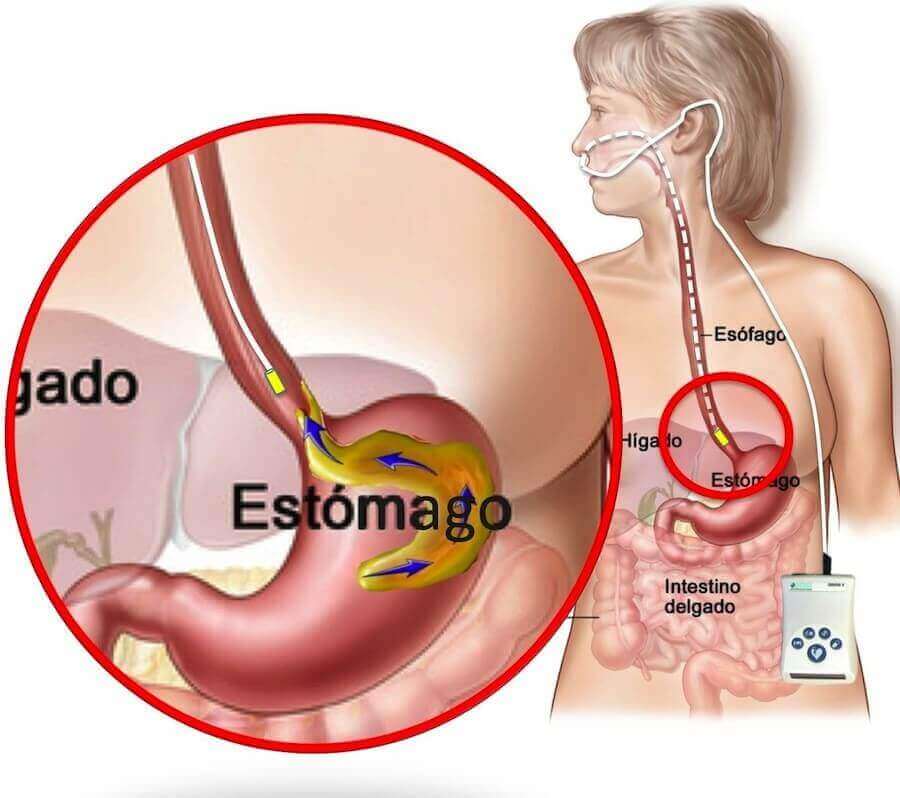

O refluxo gastroesofágico se caracteriza pela migração de parte do conteúdo do estômago (ácido gástrico e bile) para cima, em direção ao esôfago. Isto acontece diariamente em praticamente em todas as pessoas. Particularmente após as refeições, uma pequena quantidade do líquido comumente reflui do estômago para o esôfago e é chamado de refluxo fisiológico, não caracterizando nenhuma doença. O refluxo gastroesofágico fisiológico não causa problemas, pois sua freqüência e duração são curtas e porque a saliva que deglutimos “lava” o esôfago constantemente.

Na transição esofagogástrica, ou seja, no final do esôfago, existe uma estrutura muscular semelhante ao ânus chamada de esfíncter esofágico inferior (EEI). Quando deglutimos o alimento, o EEI se abre dando passagem ao bolo alimentar. Na ausência da deglutição o EEI permanece fechado e tem um tônus (pressão) que impede o refluxo dos alimentos do estômago para o esôfago. A transição esofagogástrica deve se situar no abdome para que a crura diafragmática participe externamente deste mecanismo funcionando como uma válvula.

Quando há problemas funcionais ou mecânicos no EEI temos o refluxo gastroesofágico. Certos alimentos (café, álcool, chocolates), medicações (nitratos, bloqueadores dos canais de cálcio e beta-bloqueadores) e hormônios (progesterona) diminuem a pressão do EEI. A obesidade e a gestação também contribuem para o refluxo, pois aumentam a pressão intra-abdominal.